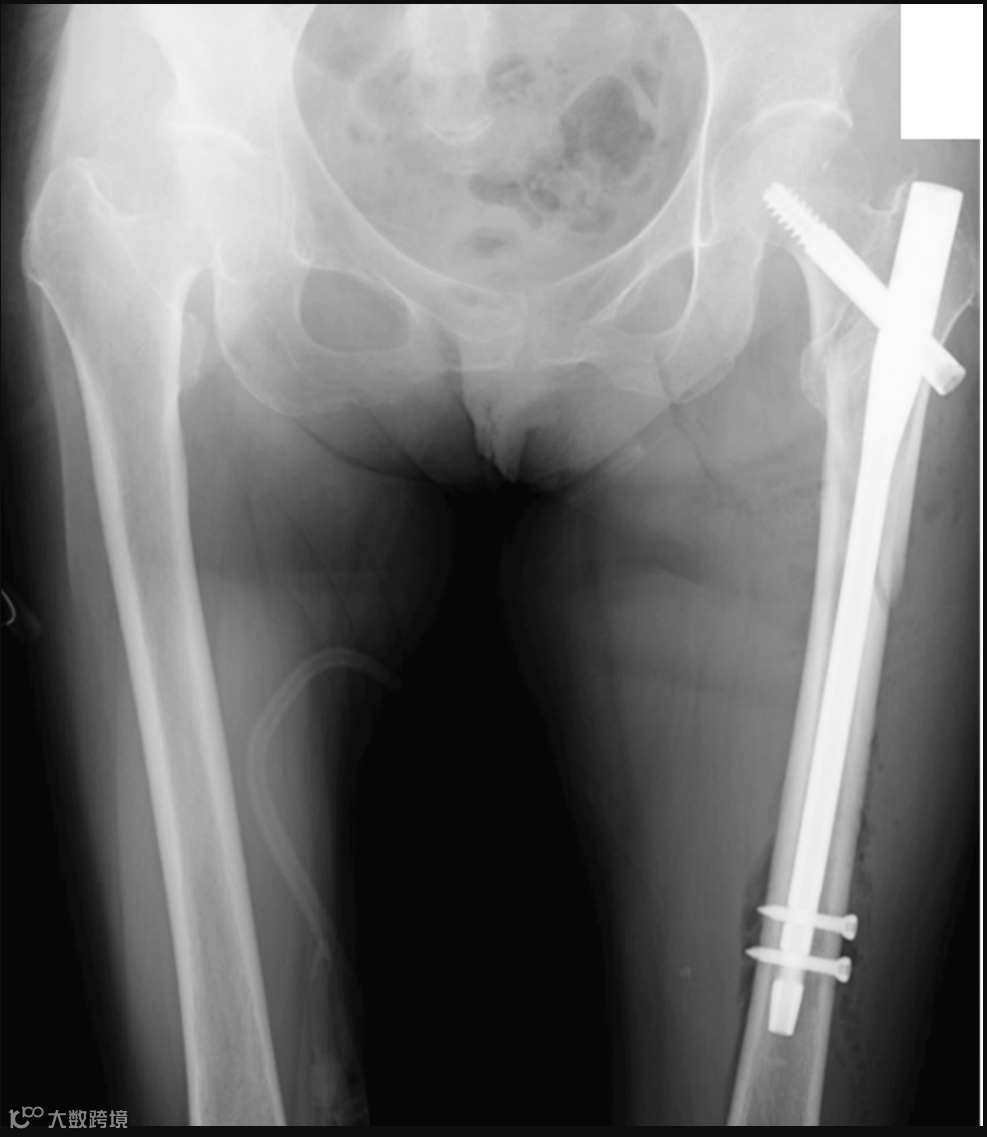

图1. 术前X线片和三维计算断层扫描图像。a. 术前X线片图像。b. 术前三维计算断层扫描图像

术前X线片和三维计算断层扫描图像未提示转移性骨肿瘤,左髋部可见近端股骨骨折(图1)。手术在牵引床上仰卧位进行,手术时间89分钟,估计失血量110 ml。手术使用了IPT-EF钉,并采用NESPLON缆索系统进行转子下固定(图2)。术后次日,患者开始负重并进行步态训练。